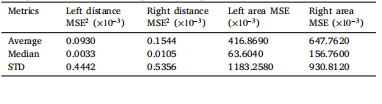

Table 3Comparison of metrics for left and right distance MSE2 and area MSE, scaled to 10−3 ,across 71 unseen test samples. Each sample consists of a predicted crown and acorresponding ground truth crown, analyzed for interpenetration distances and surfaceareas on both the left and right sides. The metrics shown include the average, median,and standard deviation (STD) for each measurement, offering insight into spatialdiscrepancies and surface overlaps across samples.

表3:在71个未见过的测试样本中,对左右距离均方误差2(MSE2)和面积均方误差(MSE)的指标进行比较,数值均已换算为(10^{-3}) 。每个样本都包含一个预测的牙冠和相应的真实牙冠,对左右两侧的相互穿透距离和表面积进行了分析。所显示的指标包括每次测量的平均值、中位数和标准差(STD),有助于深入了解样本间的空间差异和表面重叠情况。